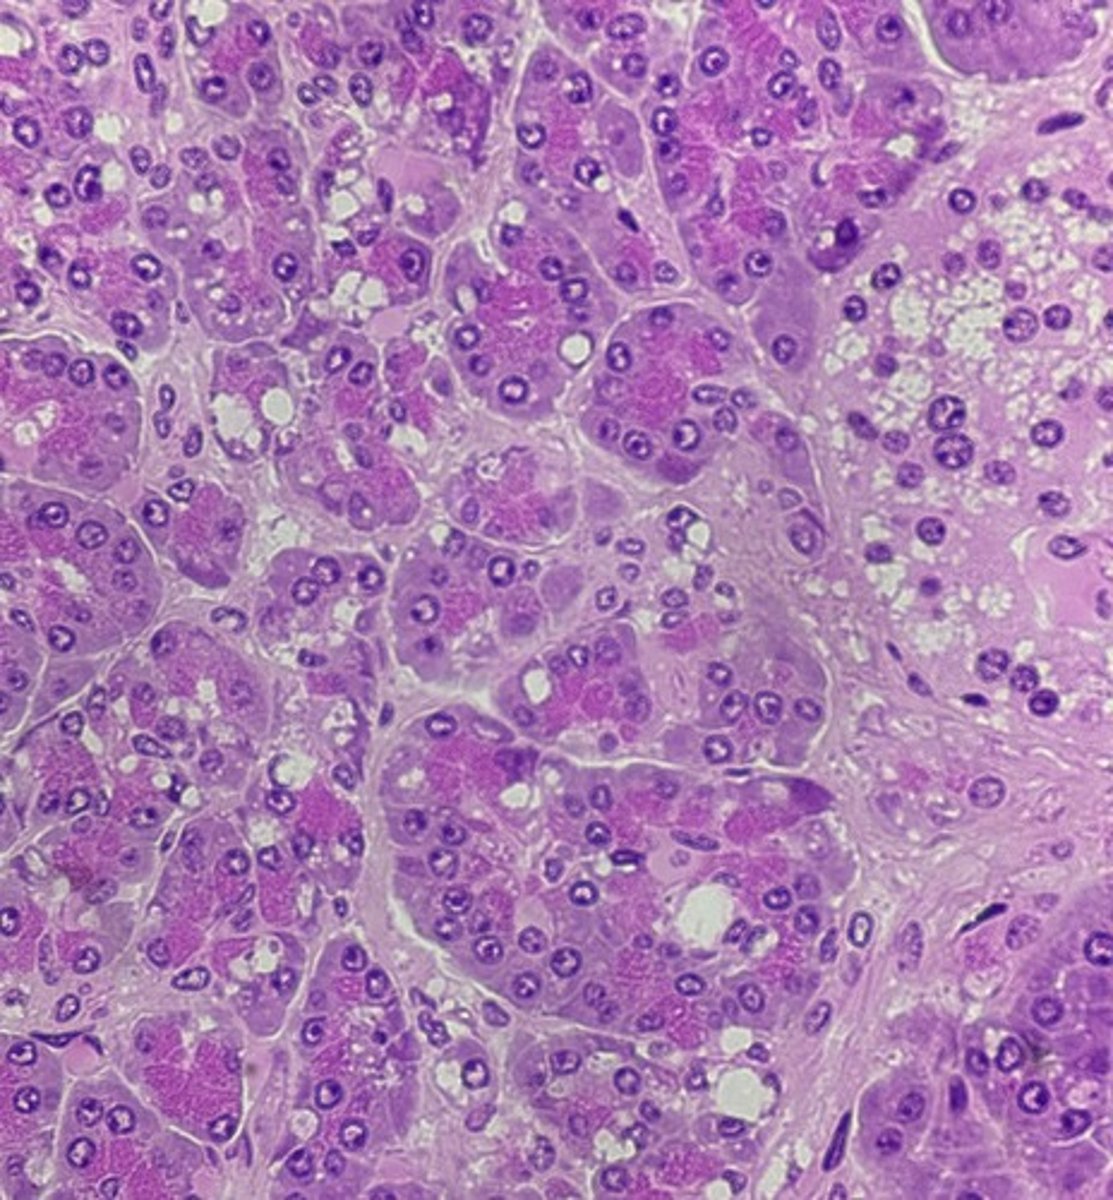

Pancreas

name the tissue

pancreatic islets

Acinar cells- digestive enzymes, amylase, lipase, & proteases

(pancreas)

type of cell & what it secretes?